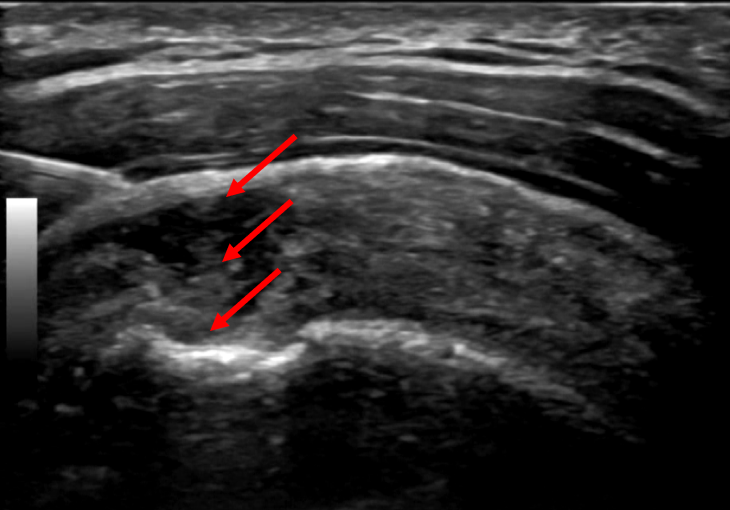

견우혈을 꼼꼼하게 확인해보니

표준 경혈 초음파 영상과 달리

까맣게 비어있는 부분이

확연하게 보었습니다.

이렇게 위-아래 전층이 비어있는 경우

염증을 빠르게 완화시켜주는

초음파 가이드 약침으로

통증 치료부터

먼저 해야합니다.